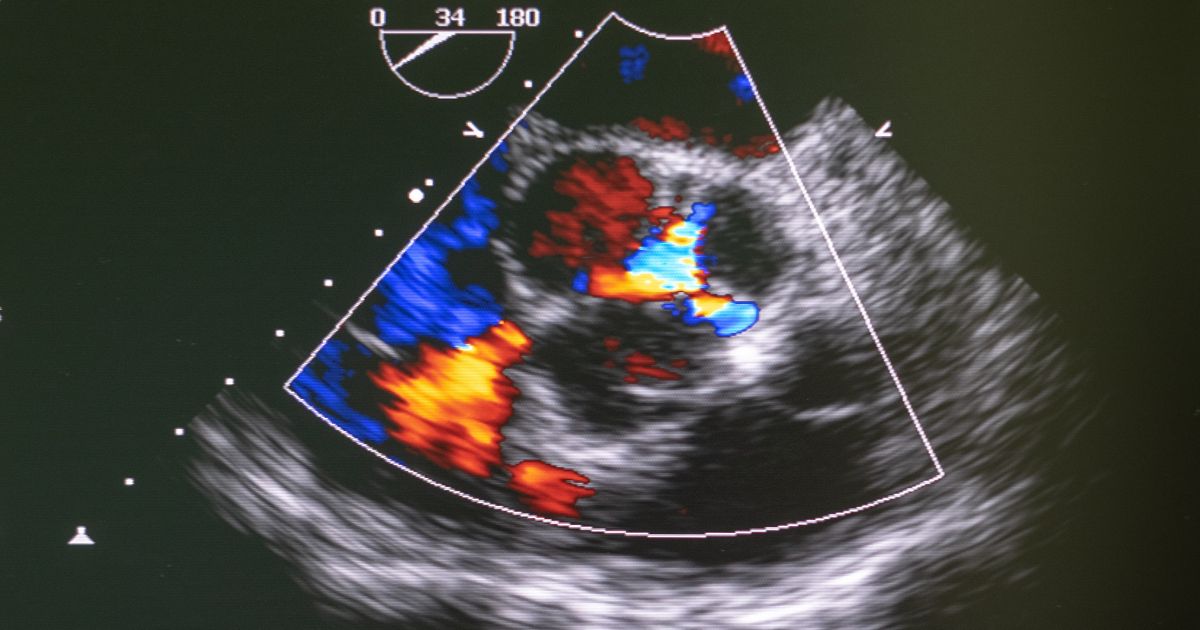

Με το τρίπλεξ καρδιάς, τίθεται και η διάγνωση ελλειμάτων στο διάφραγμα που χωρίζει τους κόλπους ή τις κοιλίες, και επομένως η ύπαρξη ανώμαλης επικοινωνίας των διαμερισμάτων της καρδιάς, που μπορεί να οδηγήσει σε διάταση και σταδιακά σε καρδιακή ανεπάρκεια. Δε σταματάνε εδώ όμως οι δυνατότητες που προσφέρει ο υπέρηχος καρδιάς. Είναι η καλύτερη μέθοδος αξιολόγησης της λειτουργικότητας των βαλβίδων, αφού έχει μεγάλη ευαισθησία στη διάγνωση της στένωσης ή της ανεπάρκειας τους.

Παράλληλα, με τη χρήση του Doppler είναι δυνατή η εκτίμηση των πνευμονικών πιέσεων καθώς και της κλίσης πίεσης διαμέσου μιας βαλβίδας, χωρίς να απαιτείται για διαγνωστικούς σκοπούς η υποβολή του ασθενούς σε επεμβατικές πράξεις, αφού αξιόπιστα δίνει αντίστοιχες πληροφορίες το triplex. Τέλος, μπορούμε να μελετήσουμε το περικάρδιο και τον περικαρδιακό χώρο (που περιβάλλει την καρδιά) για την ύπαρξη υγρού, που σε συγκεκριμένες ποσότητες μπορεί να επηρεάσει τη λειτουργία του μυοκαρδίου, και αν απαιτηθεί παρακέντηση, ο υπέρηχος μπορεί να χρησιμοποιηθεί για να καθοδηγήσει τη βελόνα στον περικαρδιακό χώρο.